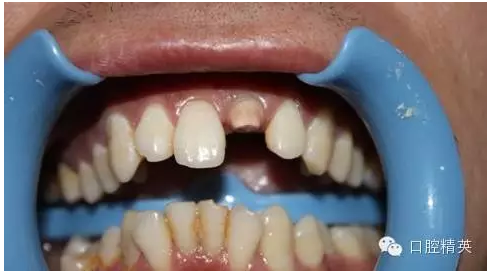

一年輕小伙,在打籃球中,被隊友打斷門牙,來本診所時已經(jīng)露髓,局麻拔髓后,行RCT。后因經(jīng)濟關(guān)系,擬鈷鉻樁加鈷鉻烤瓷冠修復(fù),備牙后才留照片:

1:牙根,備牙后,

2:唇側(cè)觀,

術(shù)前 ↑